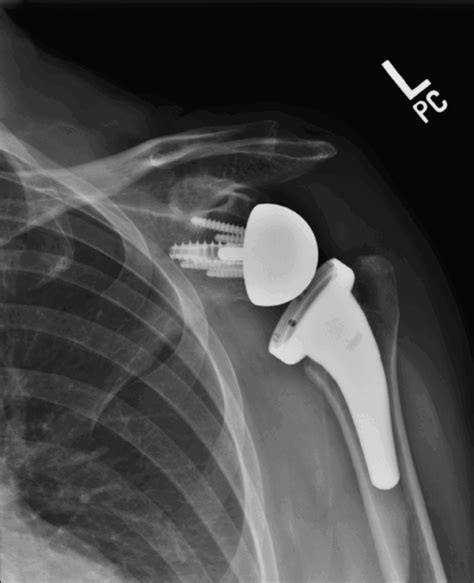

In a standard shoulder replacement, the anatomy of the joint is mimicked. However, in a reverse shoulder replacement, the “ball” and “socket” positions are essentially swapped. The surgeon attaches a metal ball to the shoulder blade (scapula) and a socket to the upper arm bone (humerus). This modification allows the deltoid muscle—rather than the damaged rotator cuff—to power the arm. Because this recovery focuses on retraining the deltoid, the rehabilitation timeline differs from standard surgeries, necessitating patience and adherence to a strict post-operative protocol.